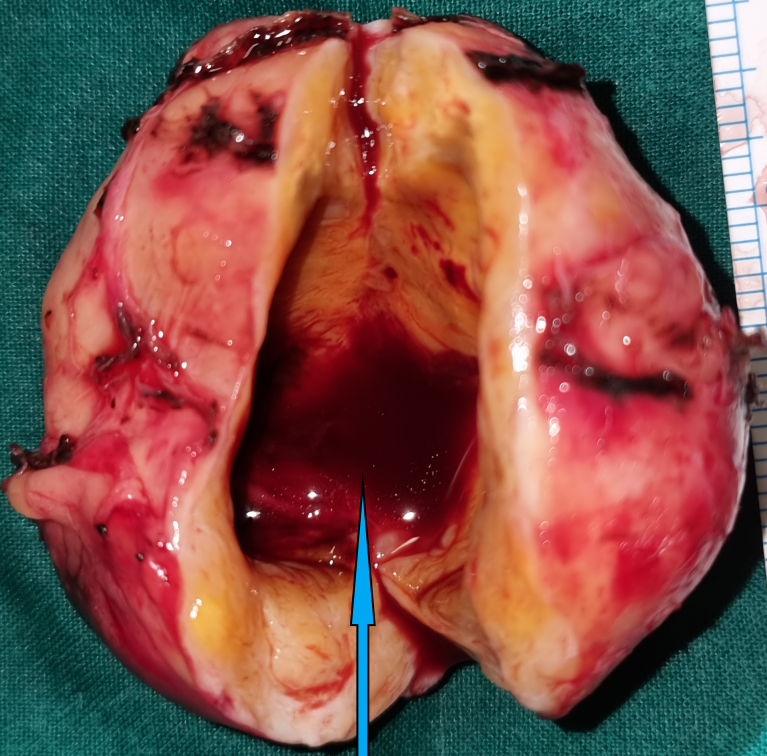

After opening of the specimen, the peripheral solid component and the central cystic component are demonstrated (blue arrow) (Courtesy Dr. V. Penopoulos)

The cystic part of the tumor contained a pale-yellow, thin fluid, odorless and sterile (Courtesy Dr. V. Penopoulos)